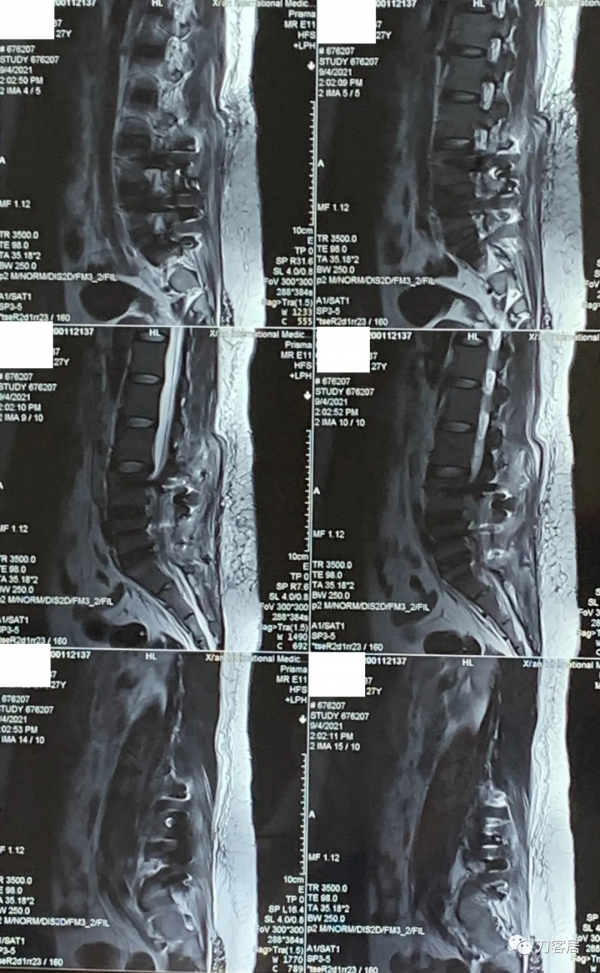

圖2. 20210817術前腰椎MRI矢狀面T2相,提示腰4-5,腰5骶1椎間盤突出,腰4-5椎間盤應該脫落進入椎管內,腰5椎體後緣了。

圖3. 20210817術前腰椎MRI矢狀面T2相,提示腰3-4-5-骶1椎間盤突出,腰3-4很輕,無需處理,腰4-5突出較大。

圖4. 20210817術前腰椎MRI矢狀面T1相,提示腰3-骶1椎間盤突出,腰4-5較大。